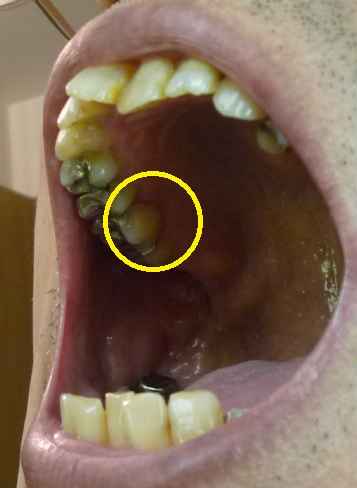

← 右上奥から2本目の内側。

歯の根もとに穴がある?

と思うのだが、医者は、たいしたことはない。と言う。

10年以上、この状態だけど良いの?と言ったら 樹脂で埋めて くれた。

ことあるごとに痛むので、気にしていたところだが、これで安心だ。